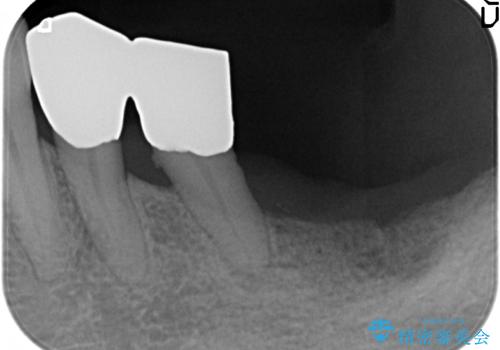

- 下の前歯(左下2)と奥歯の動揺がひどくなってきたことを主訴に来院された患者様です。

精査したところ、前歯の咬み合わせが反対になっていること、下の奥歯(下顎両側67)が4本欠損していることから動揺が生じていました。

入れ歯も抵抗があるとのことから、相談を重ね、今の状態では保存不可能な下の前歯(左下2)を抜去し、ブリッジや連結補綴により動揺を抑えることにしました。

下顎大臼歯が欠損したままで今ある歯に負担がかかりやすいことから、長期的予後は保証できないことをご理解頂いた上で治療を行いました。